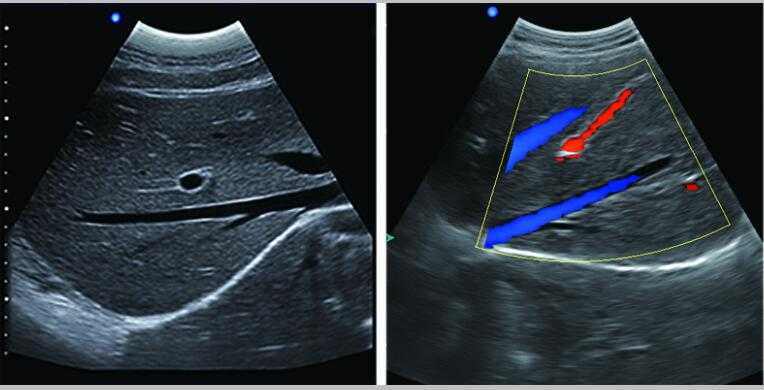

牛羊馬豬犬貓及多種家禽、實驗動物、野生動物、及部分水生動物

L3-VET便攜筆記本式獸用B超機適用探頭